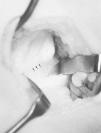

Su base es amplia y se localiza en la cara medial del húmero, a unos 5-7 cm de la epitróclea, con dirección caudal, anterior y medial,14,21 sin sobrepasar los 2 cm de longitud.14,21 En algunos casos como ocurre en el de este trabajo aparece una formación fibrosa que se dirige desde la punta de la apófisis hasta la epitróclea, conocida como ligamento de Struthers, banda supracondilar o bandeleta supraepitrocleana. Laha y cols.14 han descrito cuatro tipos en la forma de esta variante ósea dependiendo de su tamaño y de la aparición y estructura del ligamento: la forma más simple es una prominencia, que no suele producir signos clínicos; la segunda es la apófisis propiamente dicha, que puede tener expresión clínica; el tercer tipo, que correspondería al caso presentado, es la apófisis con ligamento, y por último, el cuarto tipo es la calcificación del ligamento, que formaría un foramen óseo desde la base de implantación de la apófisis hasta la epitróclea. Este último es el orificio o anillo supraepitroclear. Se ha descrito la presencia de una inserción anómala del pronador redondo,1,10,11,14 como ocurre en nuestro caso (Fig. 4), y más raramente de los músculos braquial15 y coracobraquial.1,14 Algunos autores consideran que estas inserciones anómalas pueden ser más responsables de los signos y síntomas que la propia presencia de la apófisis supraepitroclear.4 Así, la contracción del pronador redondo comprimiría el nervio mediano contra el canal y sería éste músculo la causa de la irritación nerviosa.1

Figura 4. Imagen de la apófisis una vez extirpada. En su zona más distal hay fibras musculares del pronador redondo.